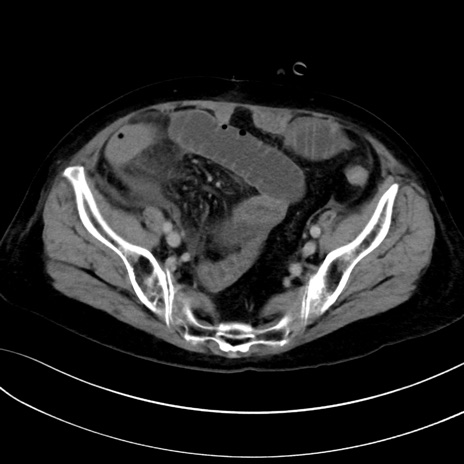

症例13 CT(横断像)1日半後